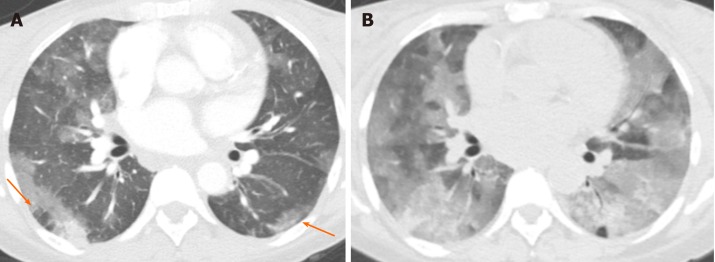

In the acute phase, bleeding into the alveoli can range from GGO to consolidation[41]. Interlobular septa may remain dark as they are not filled with blood or fluid in the acute phase. The distribution and severity of opacification can change with time (Figure 17). In the subacute phase, interlobular septal thickening can be superimposed on GGO and may sometimes cause crazy-paving appearance[7]. Subpleural sparing can be seen in both acute and subacute phases[7]. Chronic recurrent bleeding can cause ill-defined centrilobular nodules, and pulmonary fibrosis if long standing[42].

Figure 17.

Pulmonary hemorrhage. A 48-year-old woman with antiphospholipid antibody syndrome presented with shortness of breath. A: Computed tomography showed patchy, predominantly ground glass opacities in both lungs, with areas of subpleural sparing (arrows) that were confirmed to be due to alveolar hemorrhage; B: At 6 mo later, the patient presented with worsening dyspnea and hemoptysis and computed tomography demonstrated significant interval worsening of ground glass opacities with new involvement of a majority of the lung parenchyma.

Treatment of pulmonary hemorrhage is supportive and addresses the underlying etiology.